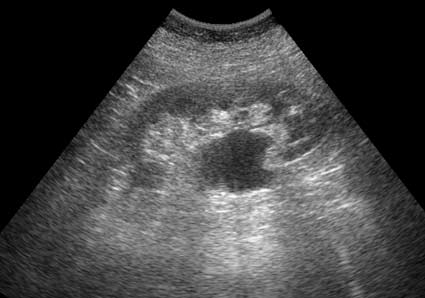

КТ с контрастированием (отсроченная фаза)

2web.jpg (13.67 КБ) 1229 просмотров